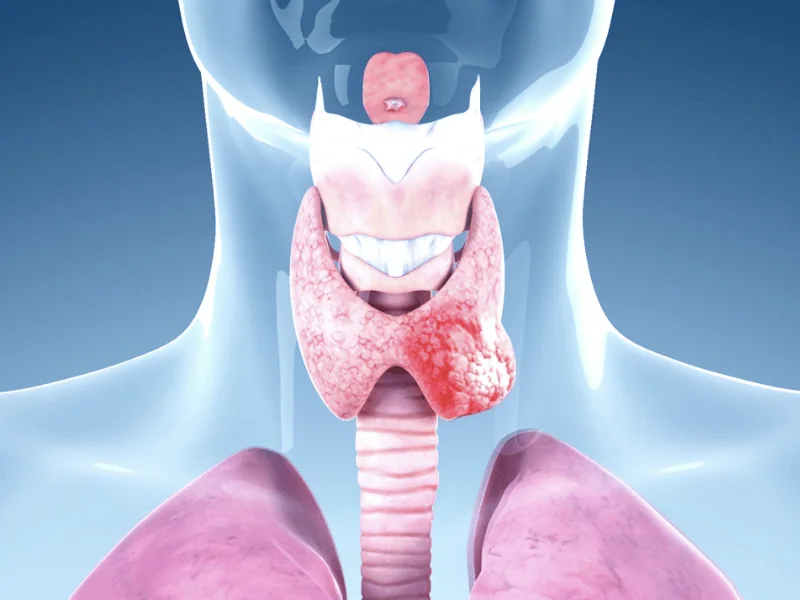

Câncer de tireoide é o mais comum da cabeça e pescoço. 95% são papilíferos (excelente prognóstico). Maioria assintomático (achado em ultrassom). Tratamento: tireoidectomia ± radioiodo. Sobrevida 30 anos: 95% (papilífero). Incidência aumentando mas mortalidade estável (microcarcinomas). Acompanhamento: tireoglobulina + ultrassom. Prognóstico depende: idade, tamanho tumor, metástase linfonodal.

Carcinoma papilífero (90%)

Características:

- Mais comum (90% dos casos)

- Cresce lentamente (anos)

- Metástase: linfonodos cervicais (30-40%)

- Raramente metástase distante (2-5%)

- Sobrevida 30 anos: 95%